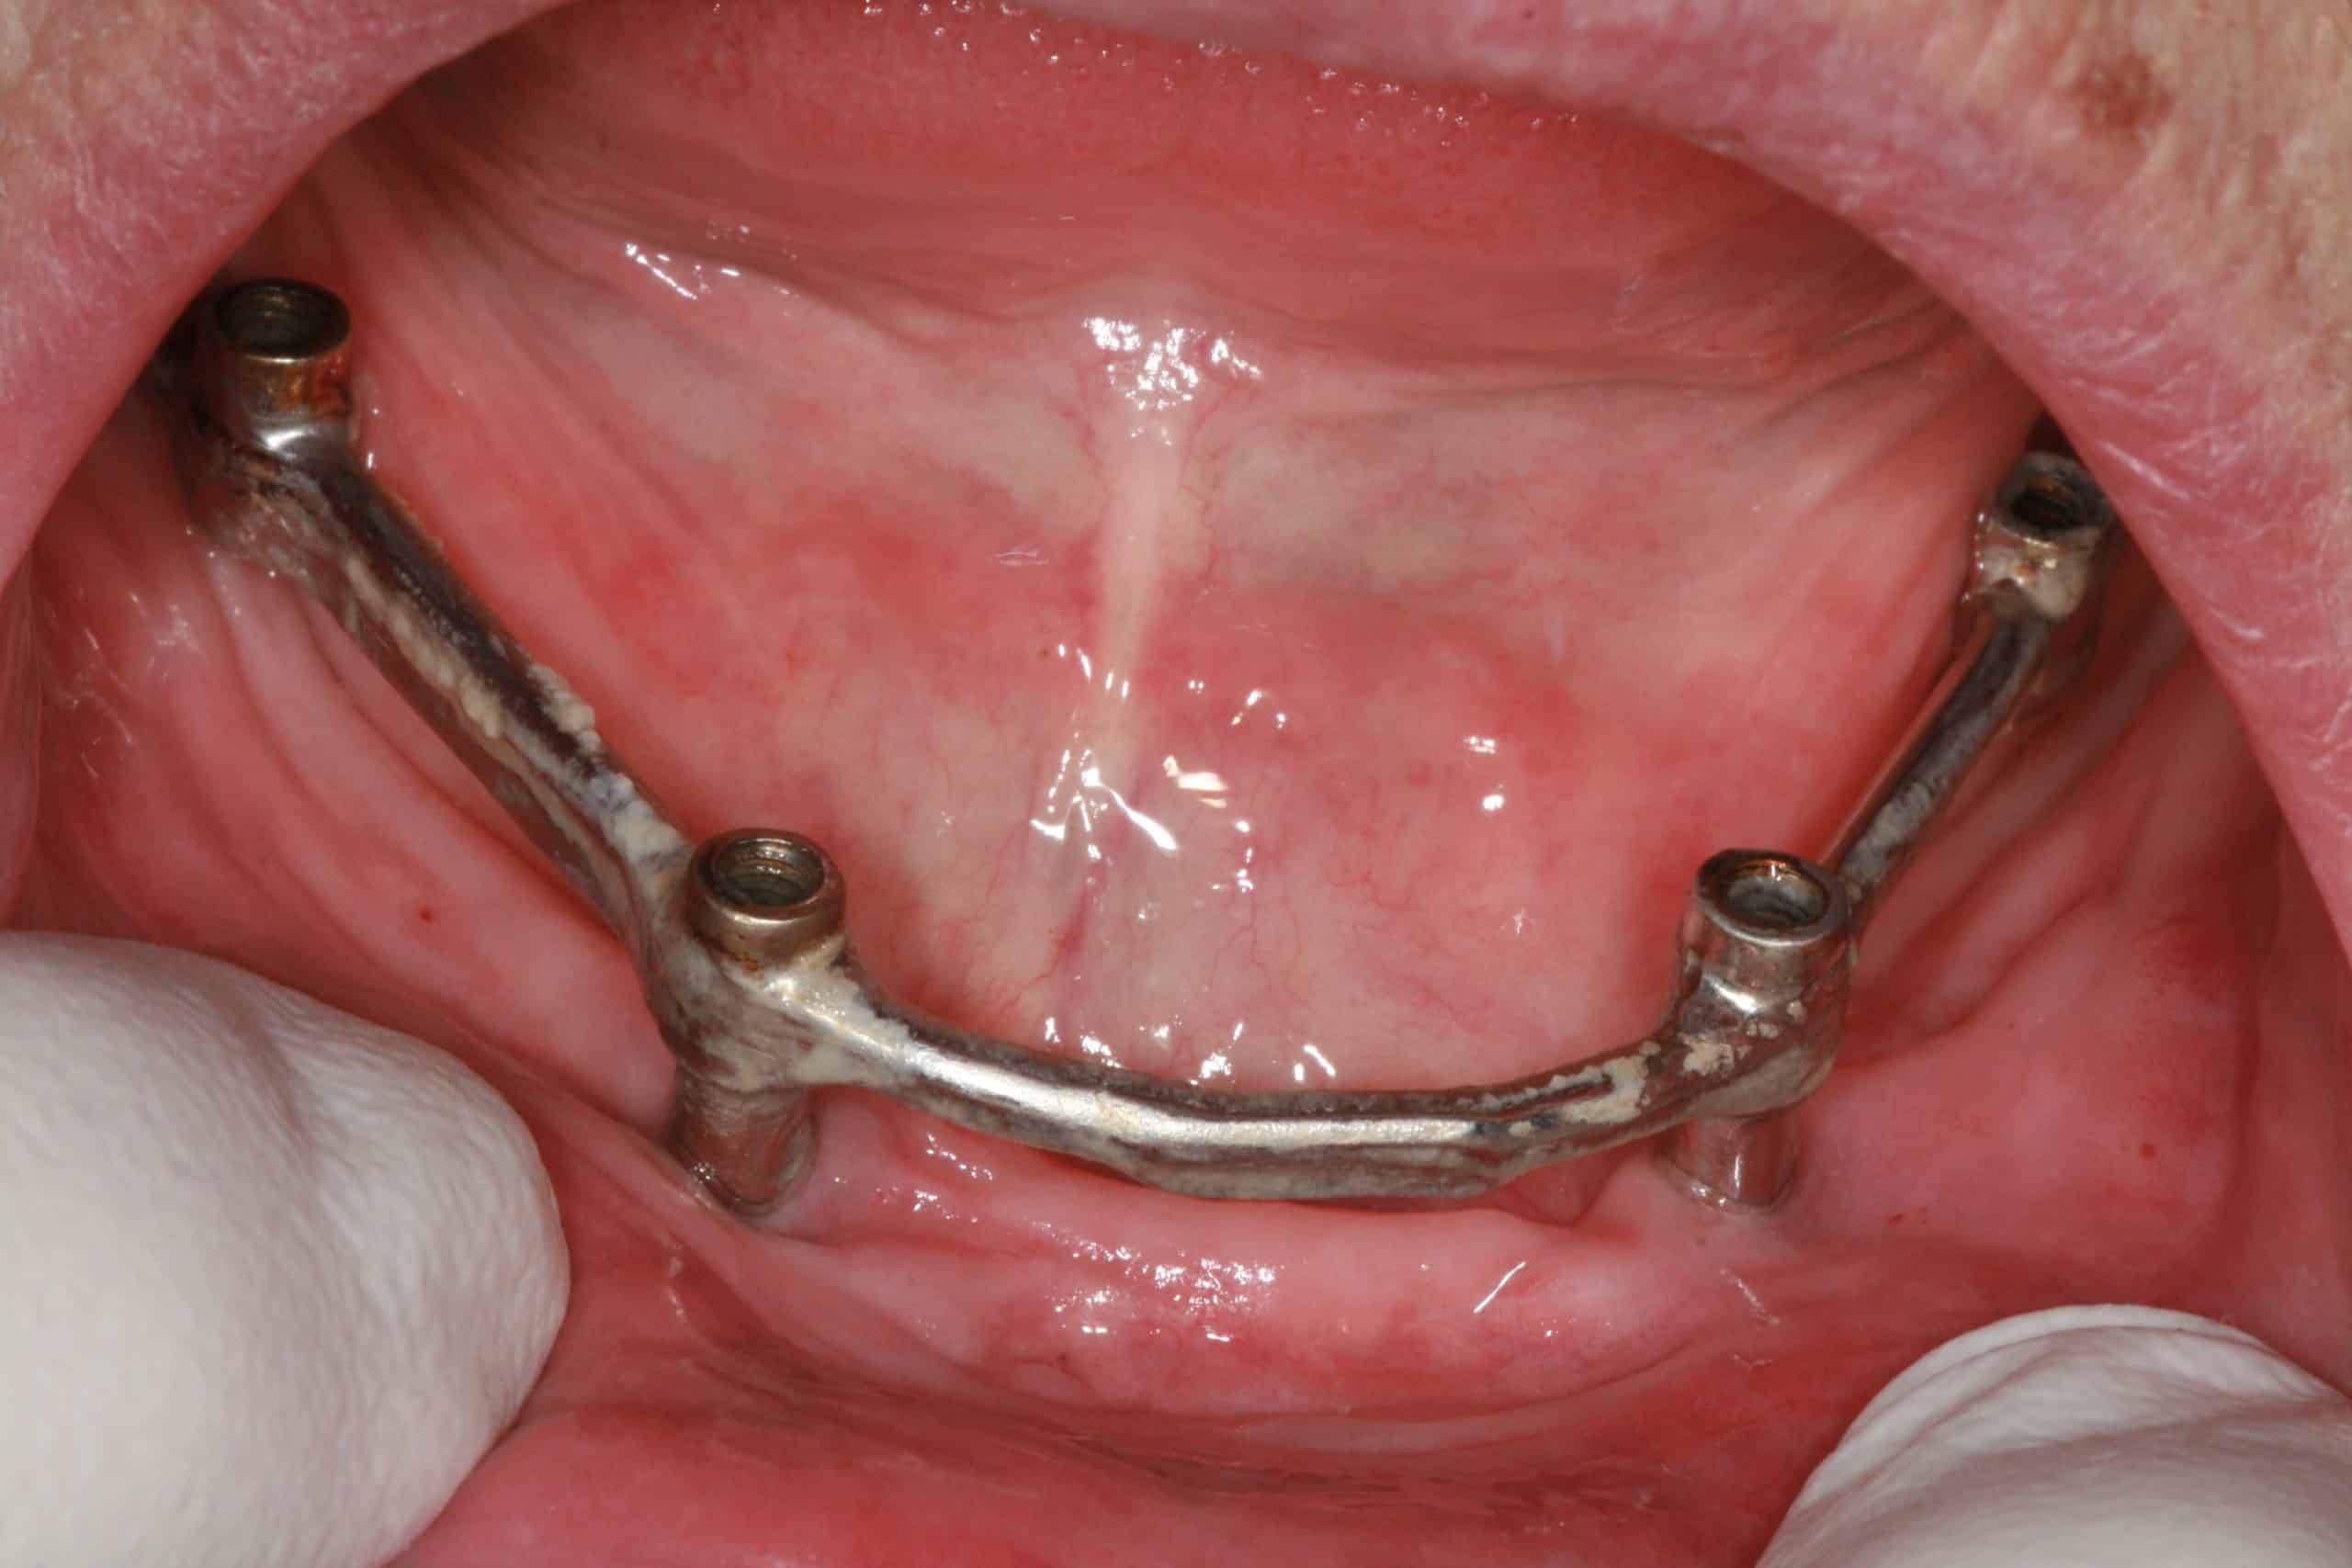

From kiserdental.com

OLD Subperiosteal Mandibular Hybrid Maintenance Advanced Dentistry Subperiosteal Dental Implants Subperiosteal implants were first described in the late 1940s and different types of this design evolved up to the 1980s. The aim of this study was to assess implant survival and complications rate of modern subperiosteal implants (cad designed and. See a case report of a patient who received a subperiosteal implant with laser and prf techniques. Customized subperiosteal implants. Subperiosteal Dental Implants.